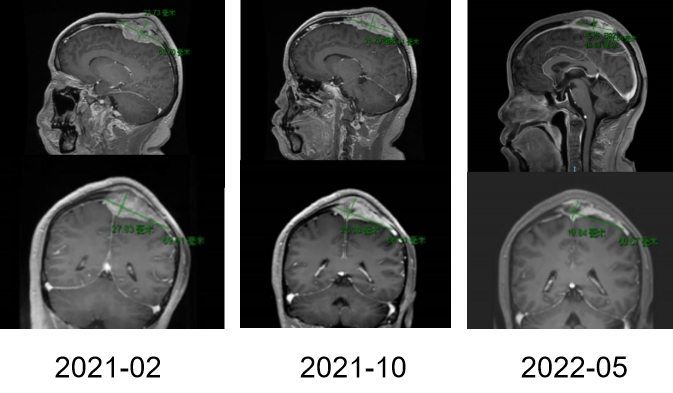

图3A

图3B